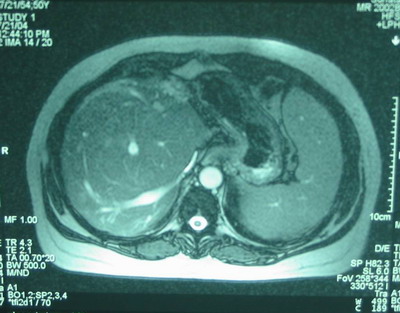

肝MRI:肝右叶异常信号――符合血管瘤肝形态,血管改变——考虑发育异常。